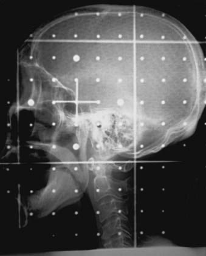

What type of image is this?

MV portal image